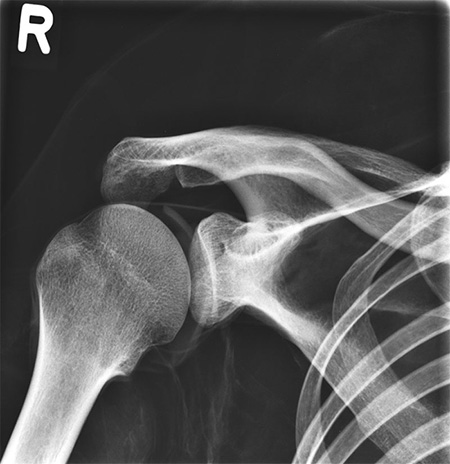

右肩旋轉(zhuǎn)側(cè)的方式,拐到水平位置。 左肩向前轉(zhuǎn)動(dòng),上到水平位置。

右肩旋轉(zhuǎn)側(cè)的方式,拐到水平位置;左肩向前轉(zhuǎn)動(dòng),上到水平位置;手肘彎曲向內(nèi)約 90度;髖關(guān)節(jié)分別向前旋轉(zhuǎn)至90度,然后旋轉(zhuǎn)向外達(dá)45度;雙膝微屈約90度;模體可以在仰臥蛙腿的姿勢(shì)舉行;頭部的支撐利于各種頭部定位;

During assembly of this phantom we pay special attention to the correct size of joint spaces. All joints are moveably mounted allow positioning in all normal x-ray positions. The arms can be moved upwards which makes the phantom suitable for use in all kinds of osseous examinations under CT.